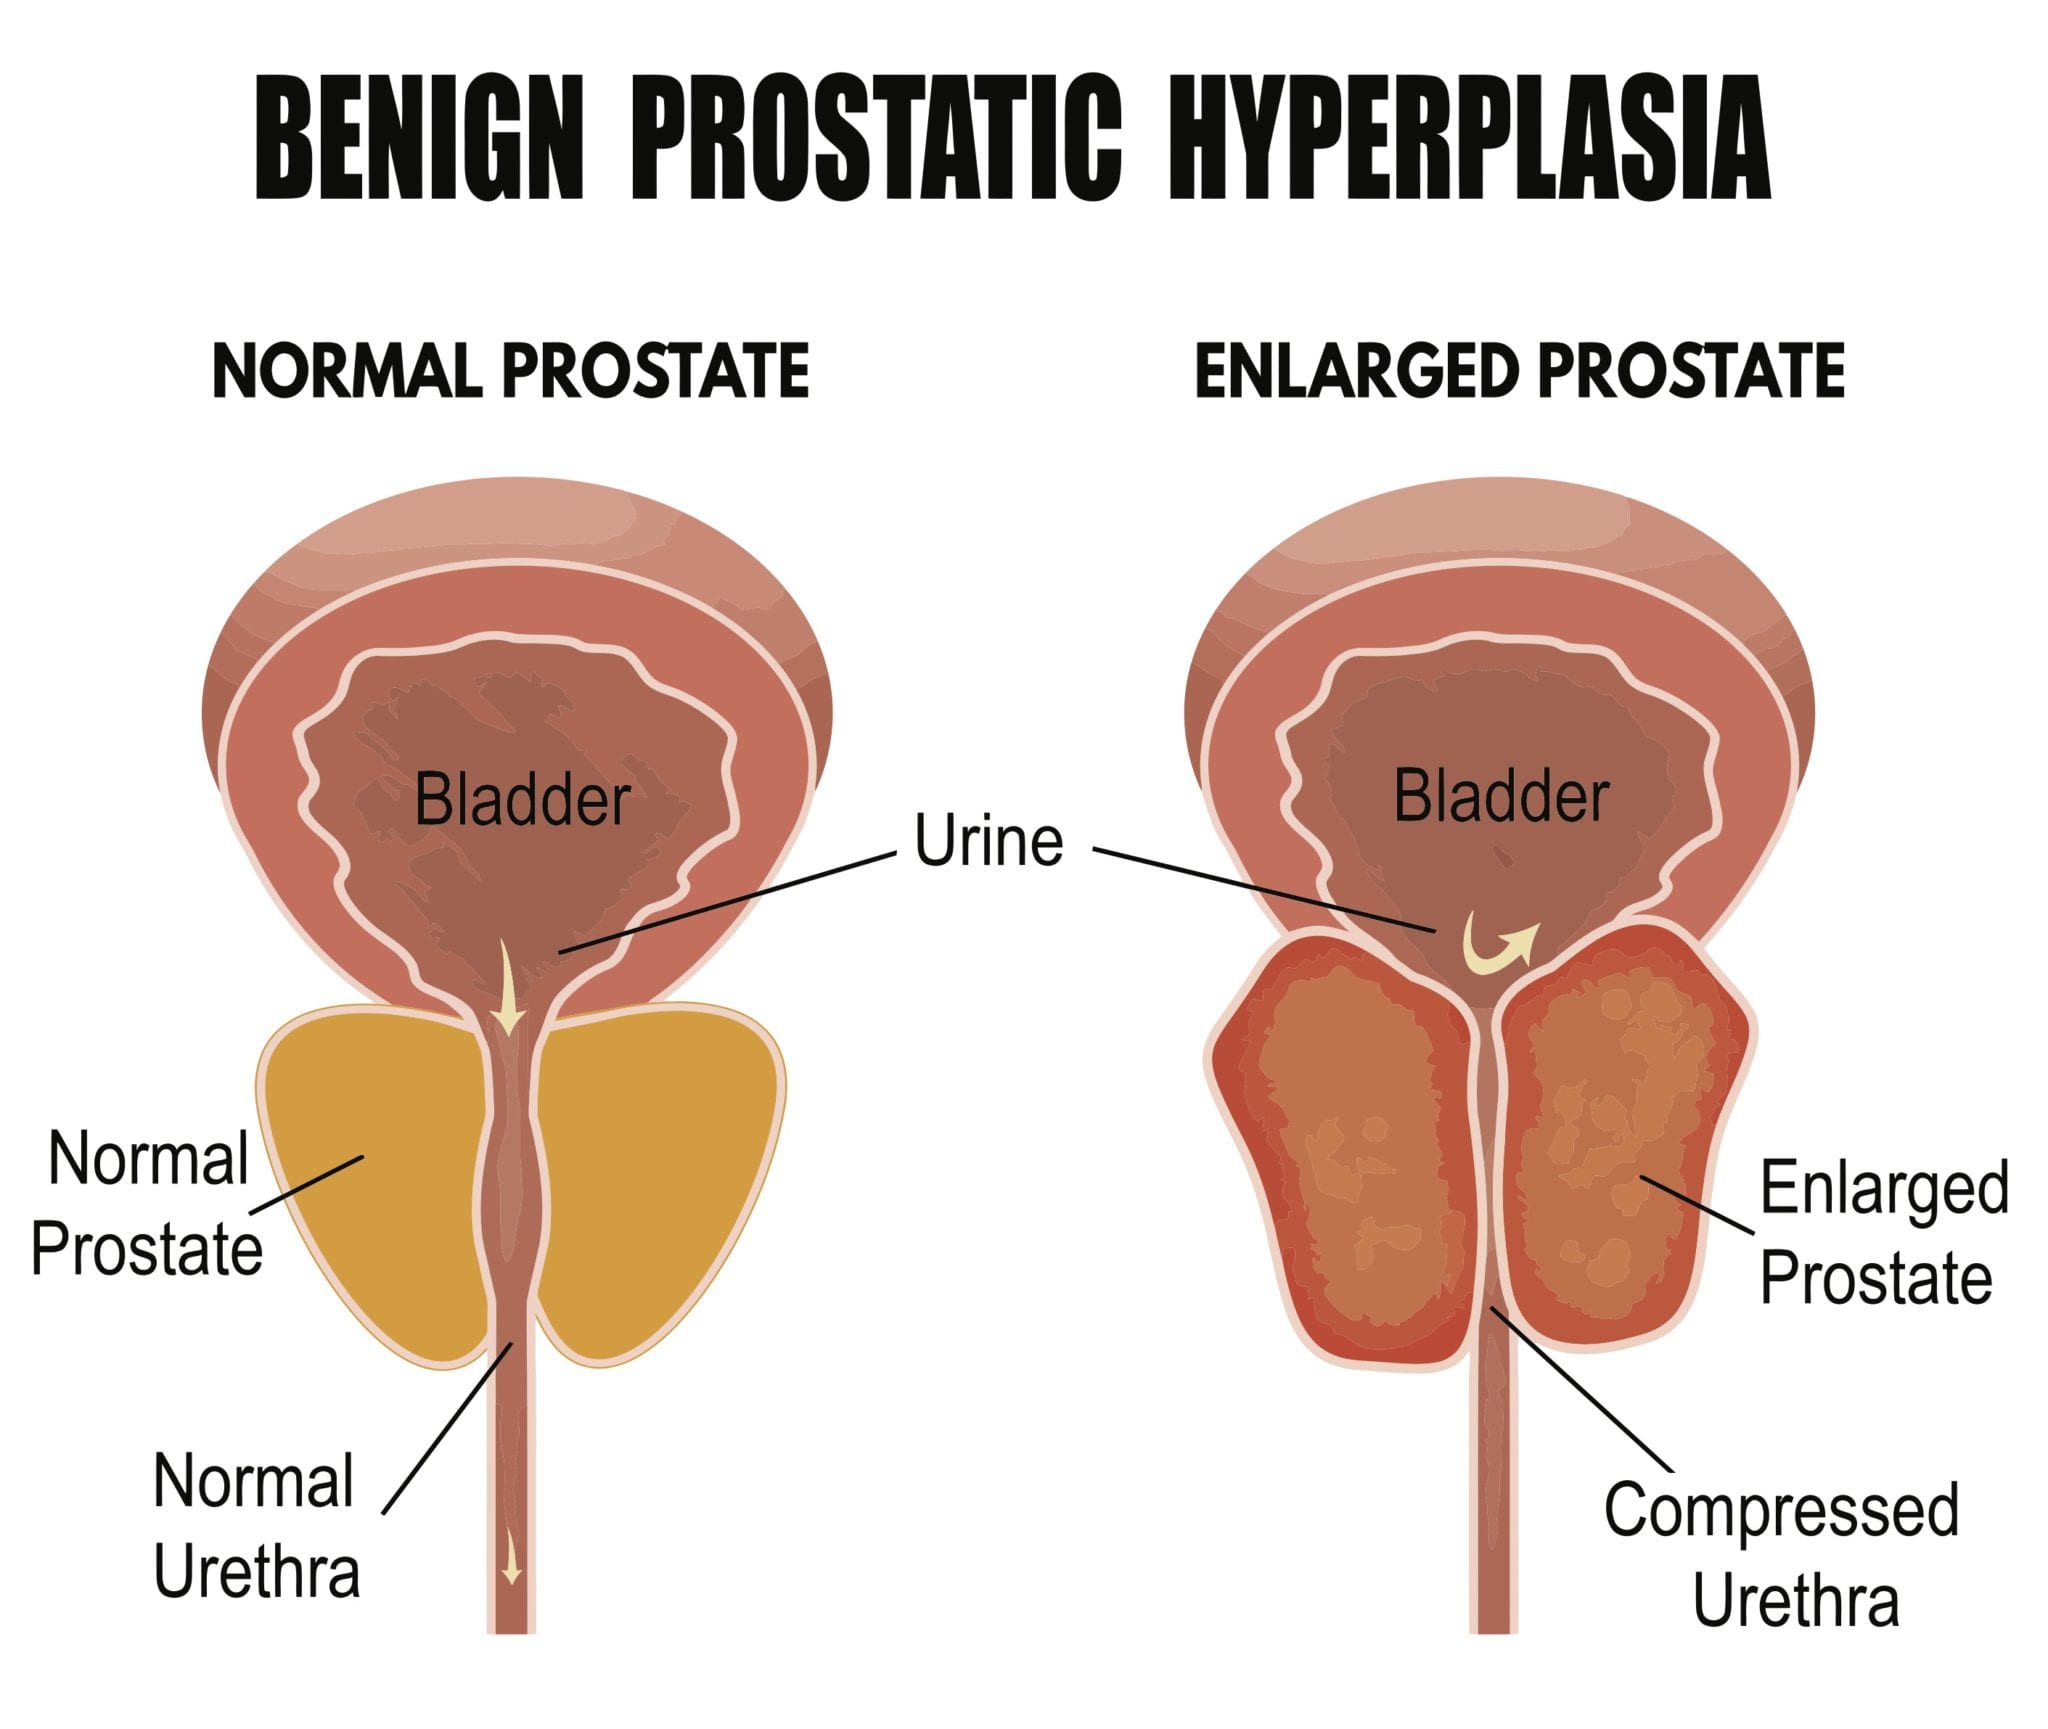

Enlarged Prostate Treatment Chattanooga TN | Laser Ablation

Understanding prostate cancer

Overview – Marie Keating Foundation